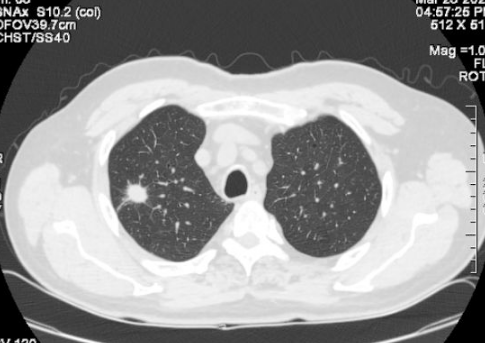

但是X线对软组织的分辨率不是很高,小于一厘米的结节很难发现。现在,越来越多的人在体检时选择胸部CT检查。这样,随着医学影像诊断技术的进步,两到三毫米的肺结节也能被发现和检测到。因此,总的来说,肺结节的发现率越来越高。

正常人群肺结节检出率因地区而异。根据目前的情况,最低可能是20%,最高可能是40%-50%,甚至70%,这可能与参与调查的正常人群有所不同。年龄不一样。 30-70岁的正常人可能会发现70%的人有肺结节,一般在20%-40%左右。肺结节发生率高,但恶性程度低。有可能90%以上的肺结节是良性结节,最终诊断为恶性肿瘤的约有5%左右。